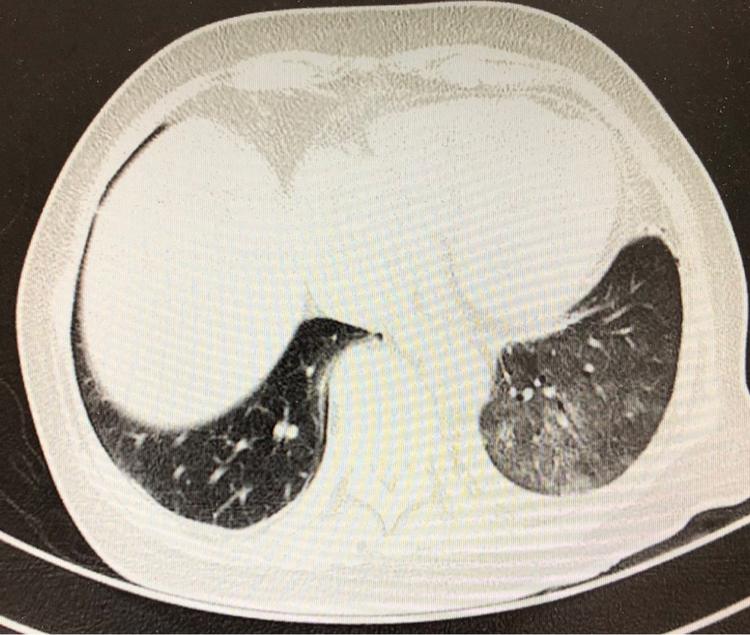

病例展示系列3复张性肺水肿

ct经典图谱:典型肺水肿ct